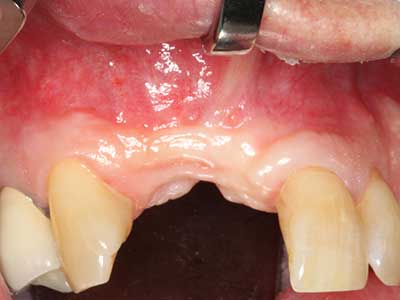

Fig. 2: Defecto del maxilar superior lateral vertical y horizontal con línea de la sonrisa alta, con indicación para la reconstrucción antes del implante.

Fig. 3: La separación basal del bloque se ve facilitada con piezas dotadas de una angulación especial.

Fig. 13: En este paciente de 52 años con una anchura del hueso residual del maxilar inferior de 4 mm, hay que asegurarse de que exista refrigeración por agua adecuada durante la partición del hueso.